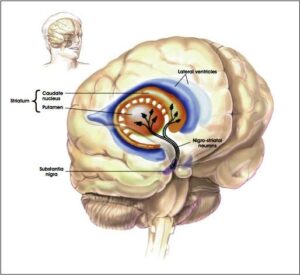

Malattia di Parkinson: Roma si conferma punto di riferimento per il Lazio nel trattamento delle patologie neurologiche Roma, 07 febbraio...